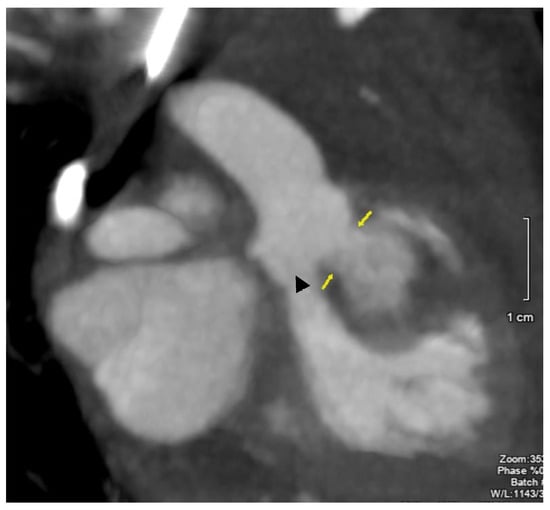

Figure 5.

Coronal visualization by CT of the aortic root. Boundaries of the ruptured right sinus of Valsalva aneurysm into the myocardial pouch is noted by the arrows. The triangle (▲) points to the location of the aortic valve leaflets.